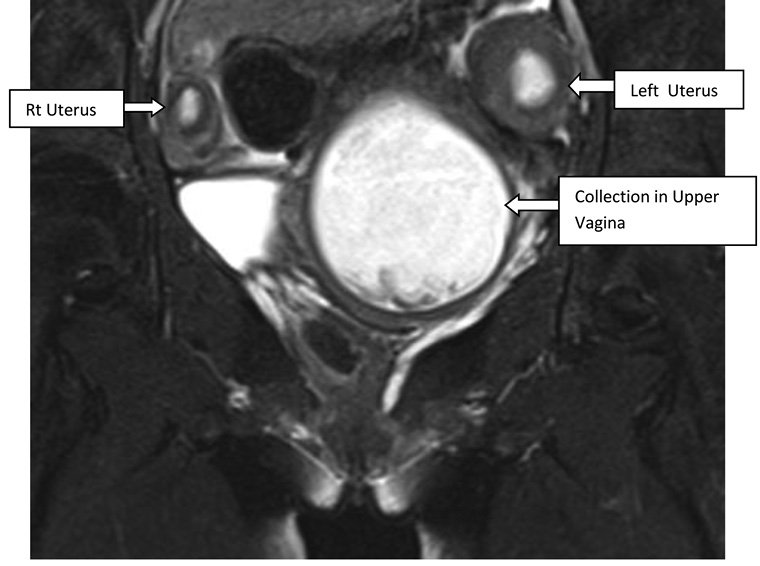

A 16-year-old unmarried girl presented to theoutpatient department of Obstetrics and Gynaecology, NEIGRIHMs Shillong with primary amenorrhoea and cyclical abdominalpain for 18months.The pain was moderate to severe in intensity, spasmodic in nature, and relieved by NSAIDs. She was a known case of juvenile diabetes mellitus. On general physical examination, the patient was thin built with the development of breast along with axillary and pubic hair, classified as Tanner’s stage 4. Her vitals were normal with normal findings on respiratory, cardiovascular, central nervous system examination. Her abdomen was soft and nontender with no mass palpable. After counseling and obtaining consent from the patient and her guardians, per vaginal examination was performed using one finger, which revealed an obstruction in the proximal part of the vagina(tranverse vaginal septum). A bulge was felt towards the left side of the vagina. Perrectal examination revealed a bulge in the upper part. She was subjected to radiological evaluation to look for other anomalies in the uppergenitourinary system.Transabdominal ultrasonography showed uterine didelphys with hematometra involving the right horn and normal renal system. She further underwent an MRI pelvis, which revealed two widely separated uterus with separate cervices. Both uteri were mildly distended with blood products, lesser in the left uterus with two cervices seen. There was evidence of a vaginal septum of 4mm thickness with a distended upper vaginal cavity and collapsed lower vagina. (Figure 1, 2) Her urinary system was normal.

Figure 1. T2 coronal showing twouteruses. Upper vaginal cavity is distended with hyperintense collection